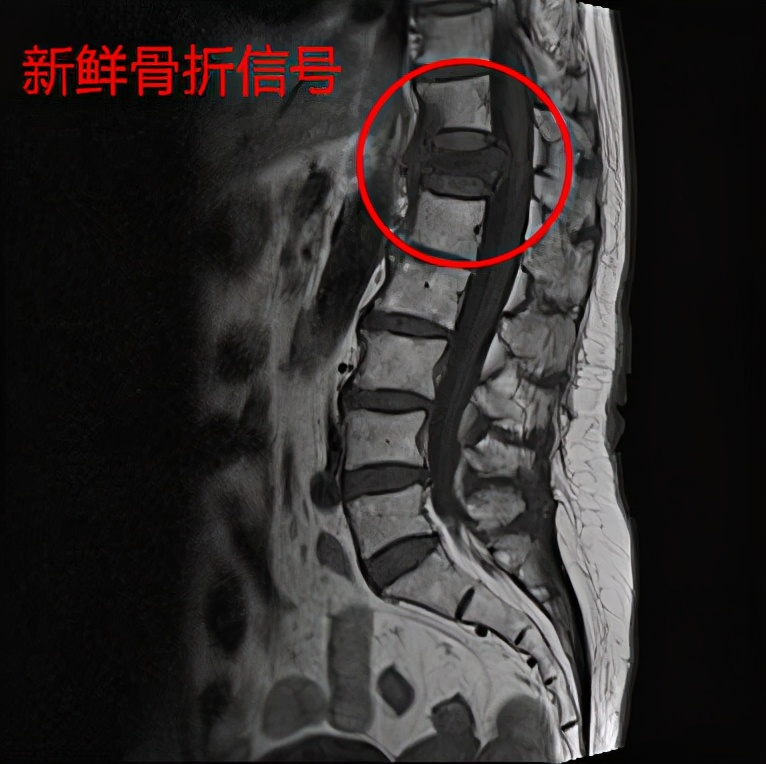

而核磁共振可以明确是否是新发生(新鲜)的骨折,因为陈旧的压缩性骨折在X线片上也是压缩性改变。